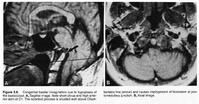

診斷:根據發病年齡、病程進展緩慢,臨床表現為枕骨大孔區綜合徵及特有的頭部外貌,藉助X線檢查多可診斷。但是,值得提出的是上述各種測量值,在男女之間、小兒之間存在著差異因此,測量數值不是絕對準確,故診斷顱底陷入時,應全面觀察顱底枕骨大孔區有無骨質改變及臨床體徵等綜合分析做出診斷。CT掃描和MRI的臨床套用,對診斷顱底陷入有了突破性進展尤其是MRI對於下垂的腦結構和合併的其他畸形,可以將其清晰地顯示出來,有助於顱底陷入的早期診斷其中對下疝的小腦扁桃體和合併脊髓空洞症顯示清晰,是常規X線檢查所不能做到的。